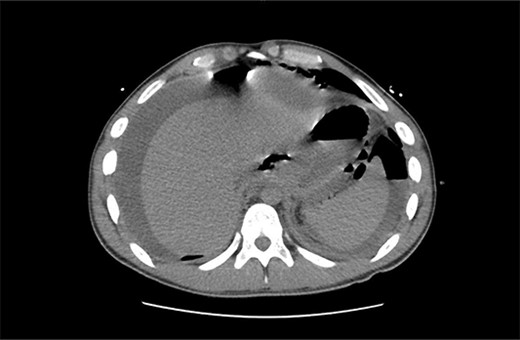

Total Parenteral Nutrition (TPN) was commenced immediately post-operatively. His post-operative course was complicated with fevers, necessitating a CT abdomen pelvis on Day 5, which demonstrated ileus with no other complications, such as ongoing leak. The endoscopic clips are noted on this CT in Fig. 4. Indeed, NG feeds were commenced on post-operative Day 7, following ongoing high NG outputs necessitating 2-hourly aspirates. TPN was ceased on Day 13, and he was discharged on Day 14 with oral antibiotics, a thickened fluid diet, and an NGT. On follow up, his NGT was removed, and he was upgraded to a full diet.

Intravenous and oral contrast enhanced CT abdomen/pelvis on post-operative Day 5, in axial view, demonstrating the placement of haemostatic clips at the previous site of perforation (arrow), with no evidence of ongoing leak.